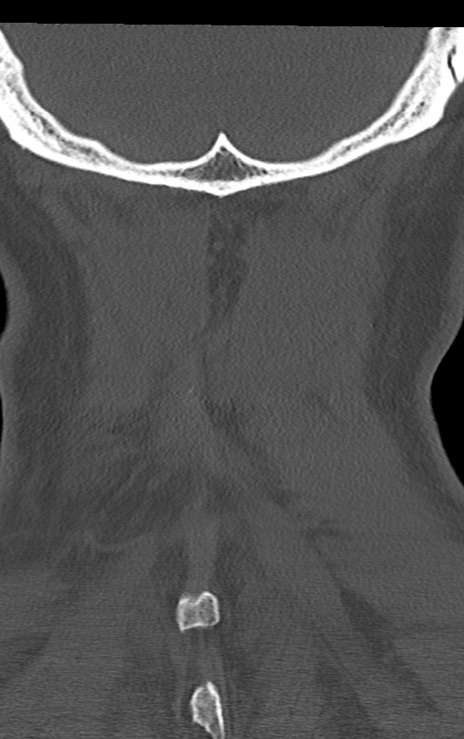

頚椎CT

矢状断像